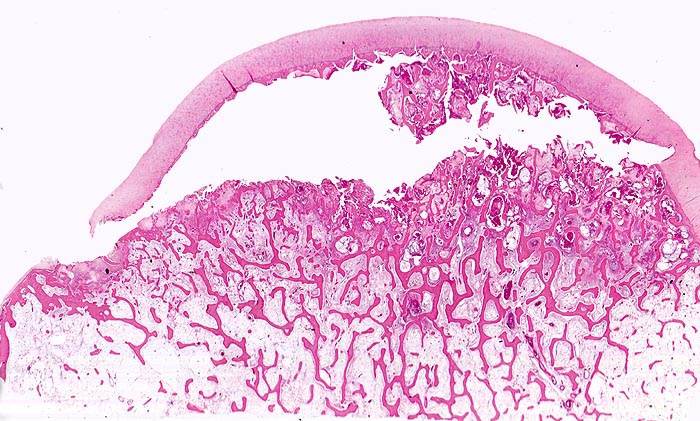

aseptische Femurkopfnekrose

Knochen, Femurkopf

Typische flächenhafte Ablösung des Gelenkknorpels zwischen subchondraler Knochenlamelle und angrenzender nekrotischer Spongiosa. Der Gelenkknorpel ist gut erhalten.

Sekundäre ischämische Knochennekrosen bei Arthrose sind im Gegensatz zur spontanen idiopathischen Knochennekrose des Erwachsenen keilförmig und weniger flächenhaft. Sie entstehen an Stellen des von Knorpel entblössten Hüftkopfes. Bei der aseptischen Knochennekrose ist dagegen der Gelenkknorpel nicht zerstört, sondern lediglich von der nekrotischen Unterlage abgehoben.